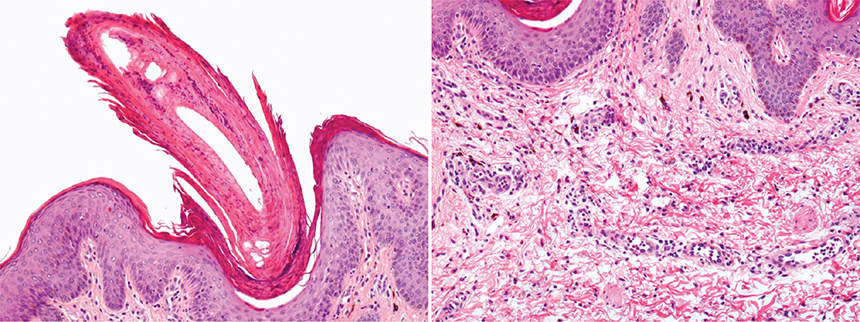

In September 2023 the patient was referred to Dermatology for hyperkeratotic folliculocentric and spiculated lesions on erythematous plaques predominantly on the face, of evolution over weeks, resembling lichen spinulosus (Fig. 1). Subsequently, she presented extra-facial extension, with lesions on the neckline, back, pubis, and proximal region of the limbs. The patient had a history of unsuccessful treatments for seborrheic dermatitis and demodicosis, including topical corticosteroids (0.1% methylprednisolone cream), 1% pimecrolimus, and oral ivermectin. Differential diagnosis between lichen spinulosus, trichodysplasia spinulosa, and spicules associated with paraproteinemia was suggested. The biopsy showed compact parakeratotic hyperkeratosis in the infundibular exit with melanophagia in the basal layer (Fig. 2) and ruled out the presence of polyomavirus and nonspecific immunofixation for immunoglobulins (4). Eventually, she developed clinical manifestations compatible with enterocolitis and gastrointestinal involvement due to GVHD.

Fig. 2. (A) Compact parakeratotic hyperkeratosis in the infundibular exit (H&E, 100×). (B) Perivascular infiltrate composed of lymphocytes in the superficial middle dermis with intense melanophagia.